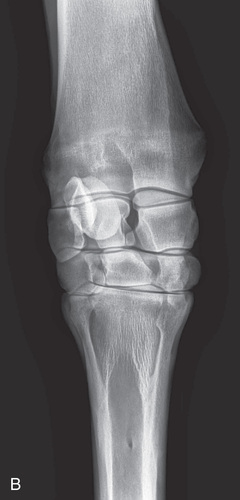

| Stifle | Lateromedial (LM) | Lateral (L) |

| Caudoproximal-craniodistal (CdPr-CrDi) | Caudocranial (CdCr) | |

Radiography of the femorotibial joint (stifle) is difficult because of the thickness of the surrounding tissue and the sensitive nature of this region. Because of the depth of the muscle in the femoral region, the caudocranial projection demonstrates little above the joint space. Radiographs of this region should be attempted only if the patient is cooperative. Safety is paramount in radiography of the hind region of the horse. Sedation or a twitch may be used; general anesthesia is also to be considered.